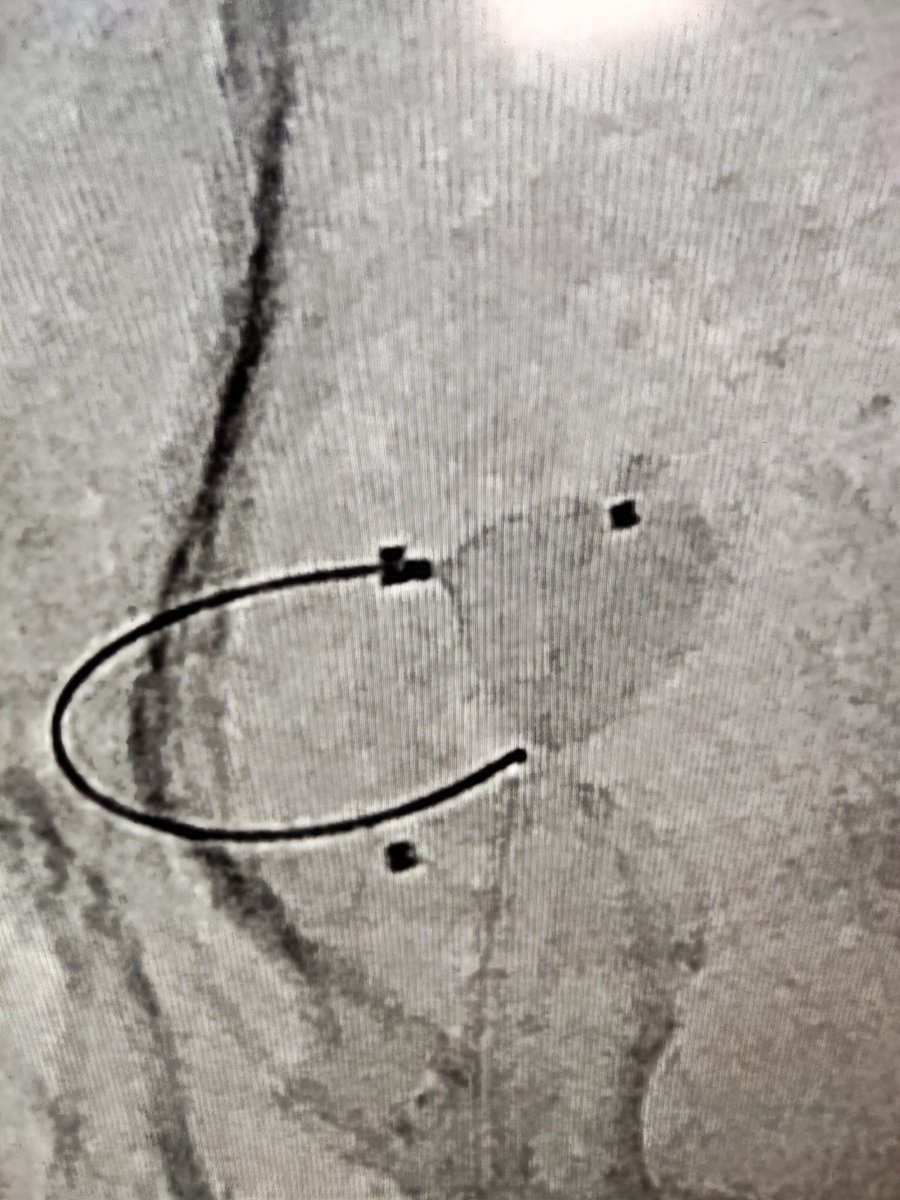

Using these new endovascular device make treating these wide neck tricky acom aneurysm safe and effective. Case of ruptured Acom aneurysm treated with transradial neqstent assisted coiling #neurointervention #aneurysm #interventionradiology

2

4

26